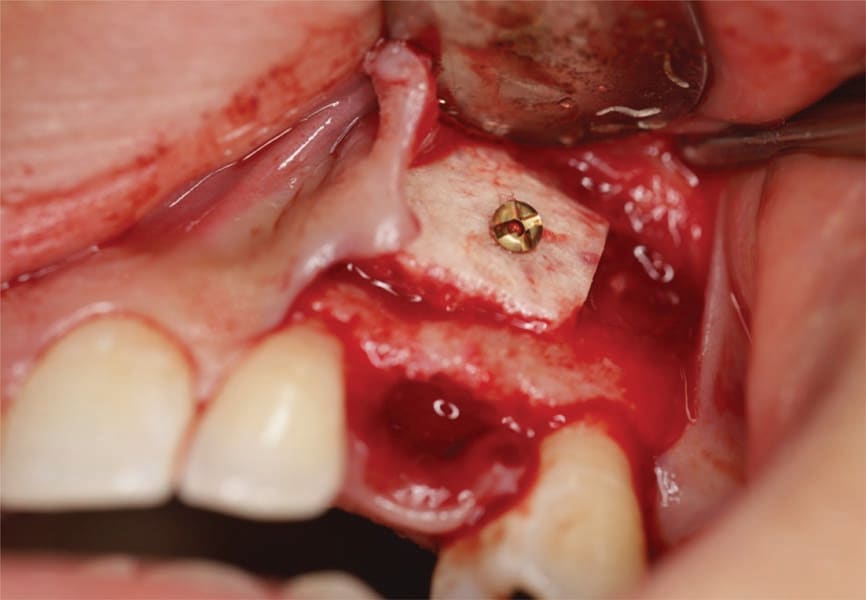

The patient presented for extraction of the deciduous canines and block grafting of the sites. Consent forms were reviewed with the patient and were signed. Local anesthetic was administered at the sites. Teeth C and I were extracted atraumatically, and a full-thickness mucoperiosteal flap was elevated at those sites (Figure 6). In this patient cortico-cancellous block grafts bilaterally were chosen (Puros® J-Block, ZimVie). The block of bone was contoured first on the cancellous alveolar side, with a football-shaped bone bur. The bone was placed in the recipient bed and was held firmly; the rest of the contouring was performed on the cortical side to allow the block to fit the site. Minimizing the thickness of the cortical bone also reduces the risk of dehiscence of the area. The cortical side was reduced significantly to allow adequate penetration of blood to allow integration and remodeling to native bone but leaving sufficient cortex to support adequate fixation. Next, using a 1.2-mm drill, the recipient site was thoroughly perforated to allow fresh bleeding and adequate penetration of the blood cells and growth factors into the graft. The graft then was firmly held against the recipient site, the 1.2-mm drill was used to place the screw hole, and a 1.2-by-10-mm screw was used to the secure the block graft into place (Figure 7). This was repeated at the left canine site (Figure 8). Particulate graft was not added so that the periosteum was in direct contact with the block to allow faster vascularization of the block graft. The periosteum underneath the flap was thoroughly scored and the flap was advanced to achieve tension-free primary closure and secured with 4-0 Vicryl sutures (Figure 9). The patient was seen for follow-up 1 week post-surgery.